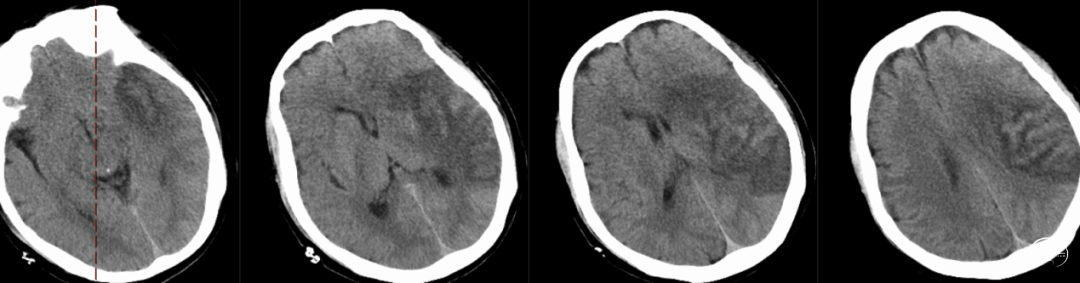

术后第1天复查头颅CT:左侧基底节及颞叶顶叶造影剂渗出改变。

术后第2天复查CT:造影剂吸收。

术后4天复查CT:左侧颞叶顶叶梗死,部分渗血改变可能。

术后复查CTA:提示左侧大脑中动脉通畅,支架在位。

➢术后14天病人恢复情况

神志清楚,可部分言语,言语含糊。查体:血压 134/80mmHg。神志清楚,GCS(E4V1M6)11分,双侧嗅觉视力检查可,双瞳孔常大等圆,D=2.0mm,对光反射灵敏,眼动可。伸舌居中,左侧肢体肌力5级,右上肢肌力2级,右下肢肌力3+级,NIHSS评分9分。